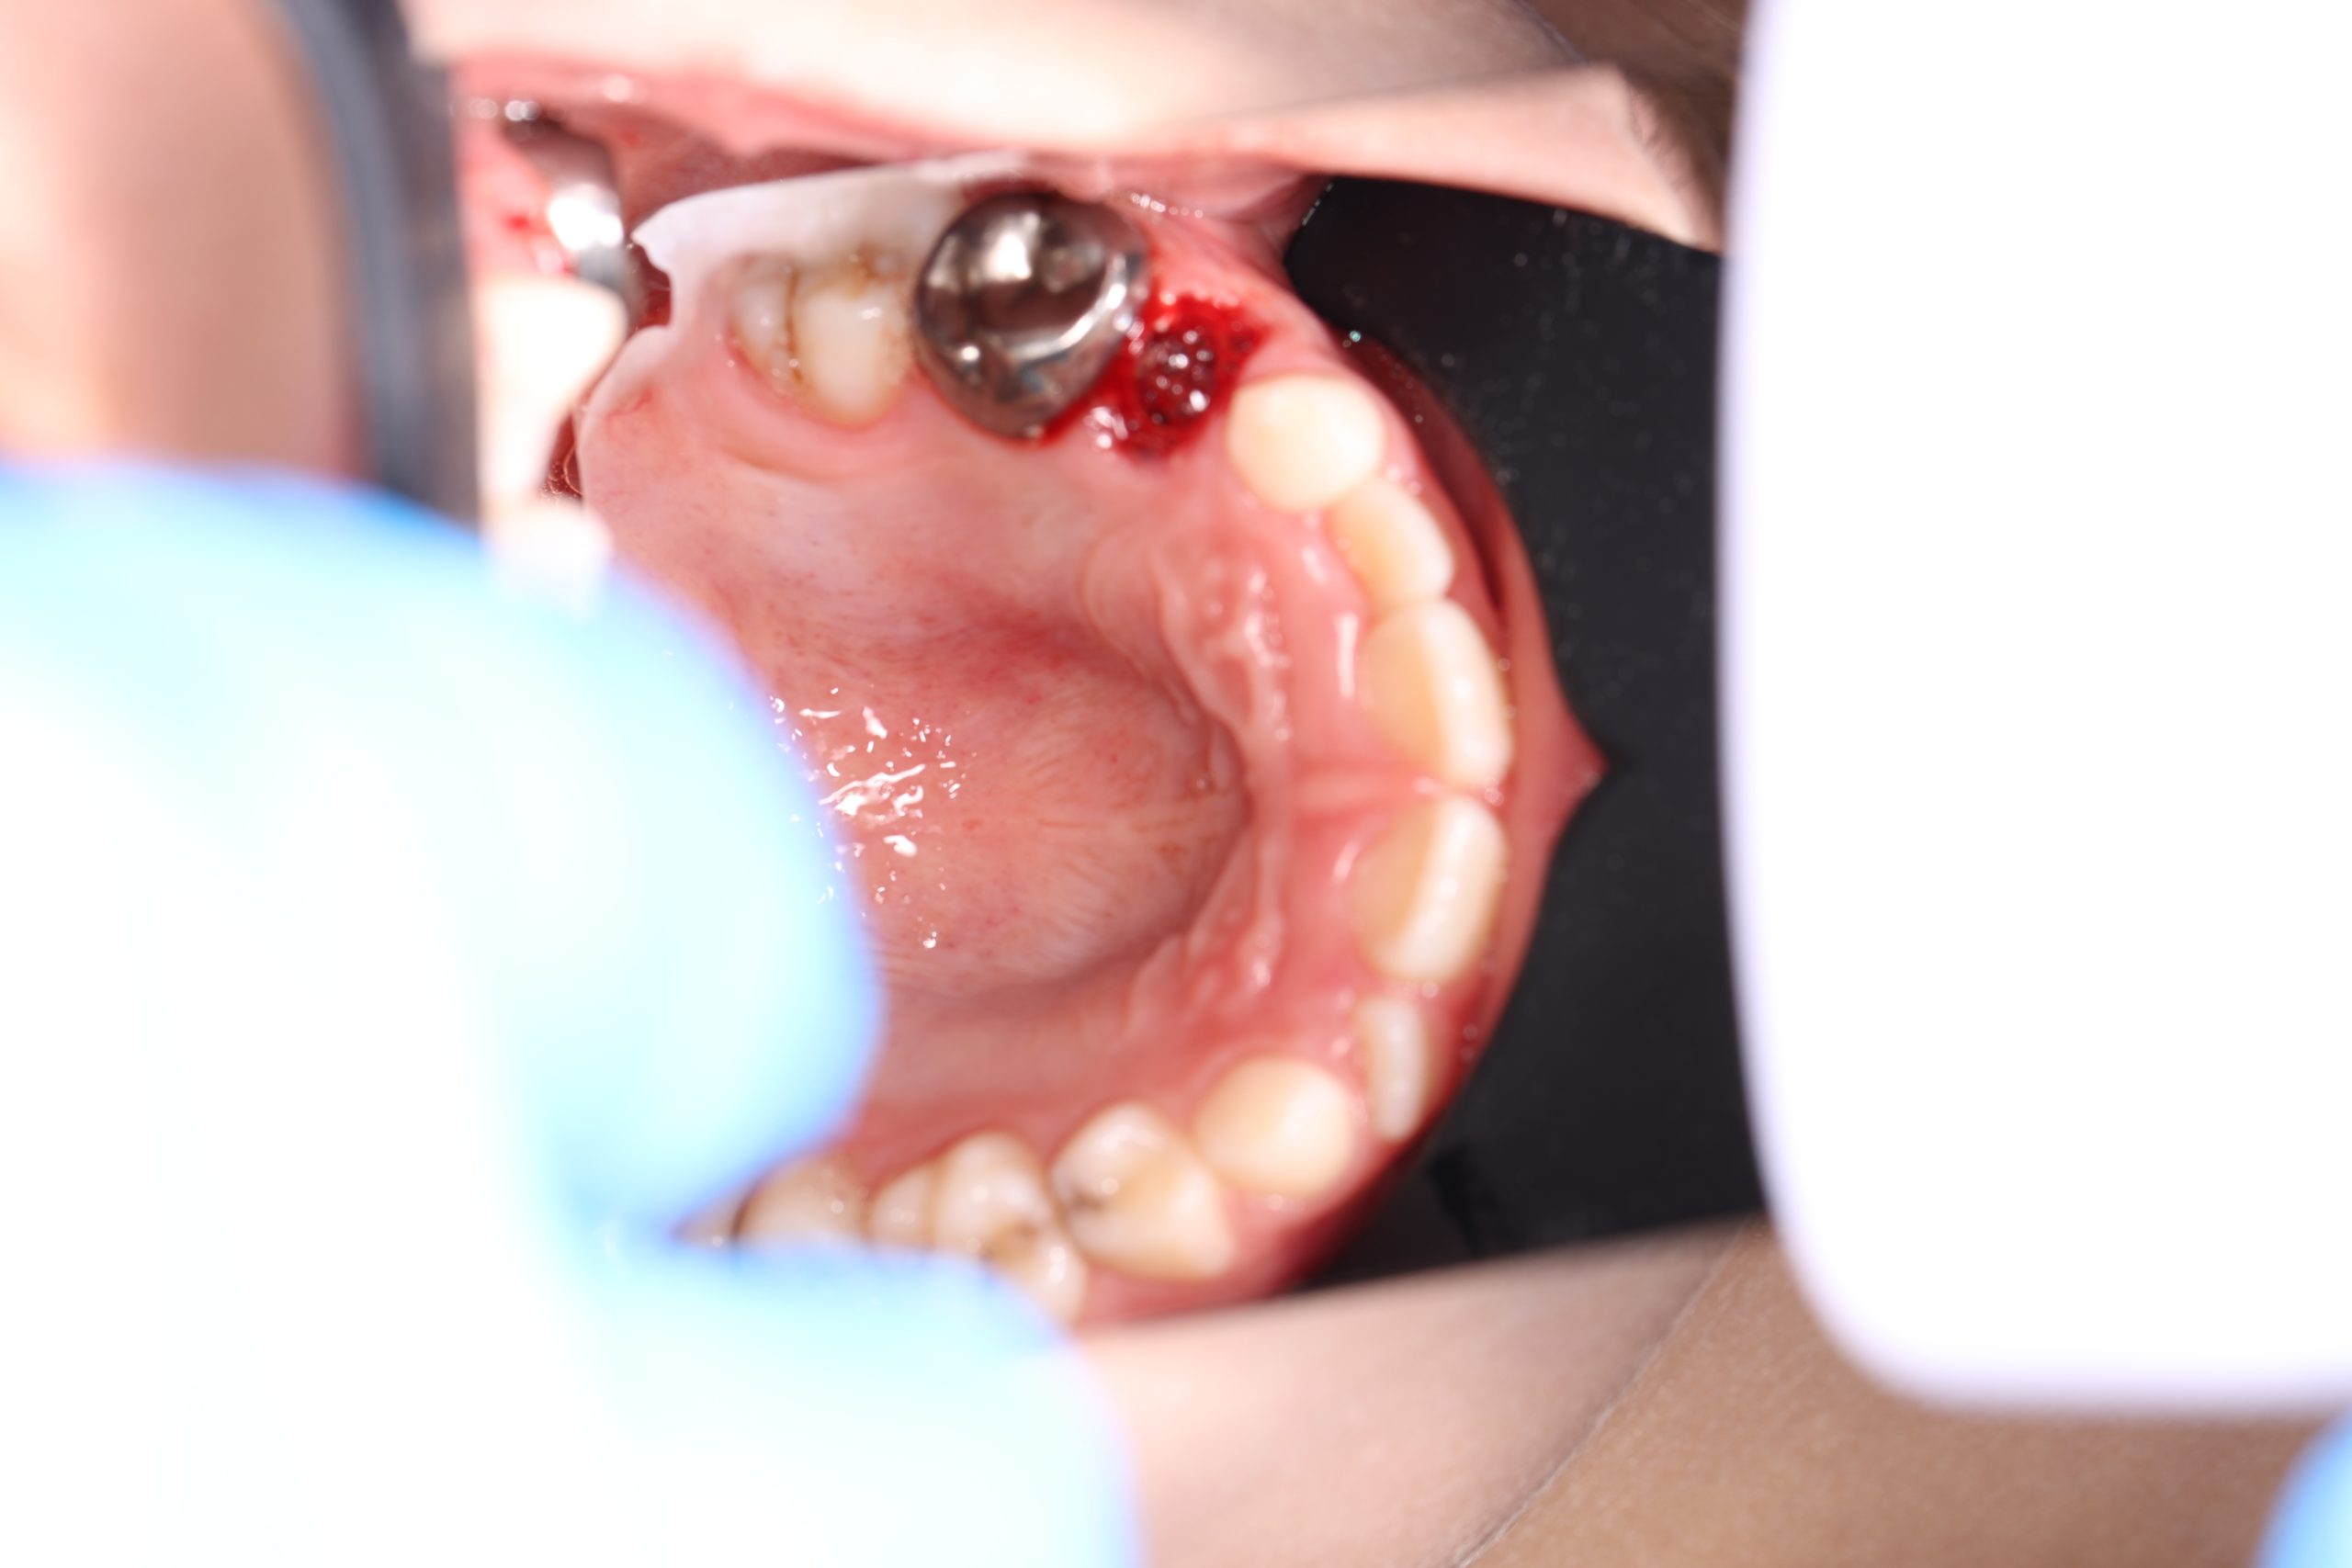

Stainless Steel Crowns (SSC)

The most popular type for back baby teeth. Durable, cost-effective, and fast to place, they provide excellent protection against further decay.

- Gentle Preparation: We do a dental cleaning and reshape the tooth under local anesthesia.

- Crown Placement: We fit and cement the crown with a strong and safe adhesive.